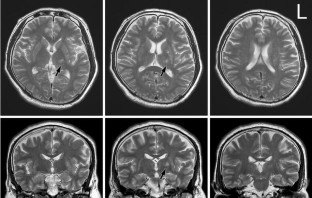

Two patients with isolated thalamic agraphia are described. Both showed kanji (Japanese morphograms) agraphia due to impaired character recall, grapheme deformity and micrographia (progressive reduction in character size during writing) after a lesion that involved the ventral lateral and ventroposterolateral nuclei. Single photon emission computed tomography with a 99mTc-ethylcysteinate dimer revealed hypoperfusion in the left precentral gyrus (Brodmann Area 6) and anterior supramarginal gyrus in both. Six months later, the extent of blood flow reduction decreased in the supramarginal gyrus in both patients and the precentral gyrus in patient 1. By this time, the writing impairment improved to nearly the normal range. Our study suggests that kanji agraphia (corresponding to lexical agraphia in Western countries) with poor grapheme formation and micrographia arises from a lesion in the ventral lateral and ventroposterolateral nuclei in the left thalamus. The accompaniment of poor grapheme formation and micrographia may reflect disruption of the cortico-subcortical motor circuit involving the putamen, thalamus, premotor cortex and sensorimotor cortex. It is also suggested that multiple cortical sites can be a target for secondary dysfunction that yields agraphia in a thalamic lesion, and that the recovery of reduced cortical blood flow does not always proceed in parallel with that of agraphia.

Fig. 1